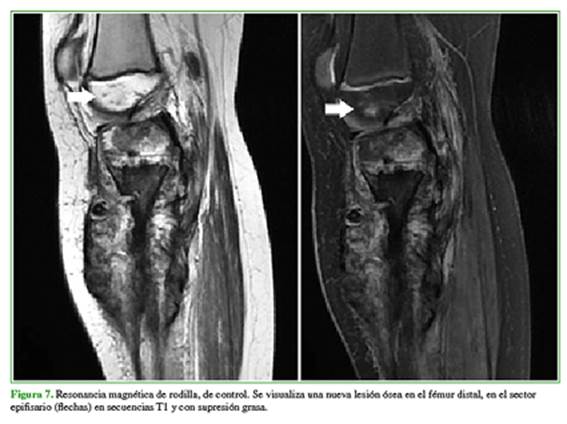

La enfermedad de este paciente progresó con metástasis pulmonar, y se decidió continuar con esquema quimioterápico ampliado. Una nueva estadificación por resonancia magnética (Figura 7) mostró una nueva lesión ósea en el fémur distal, por lo que se sugirió la amputación supracondílea.